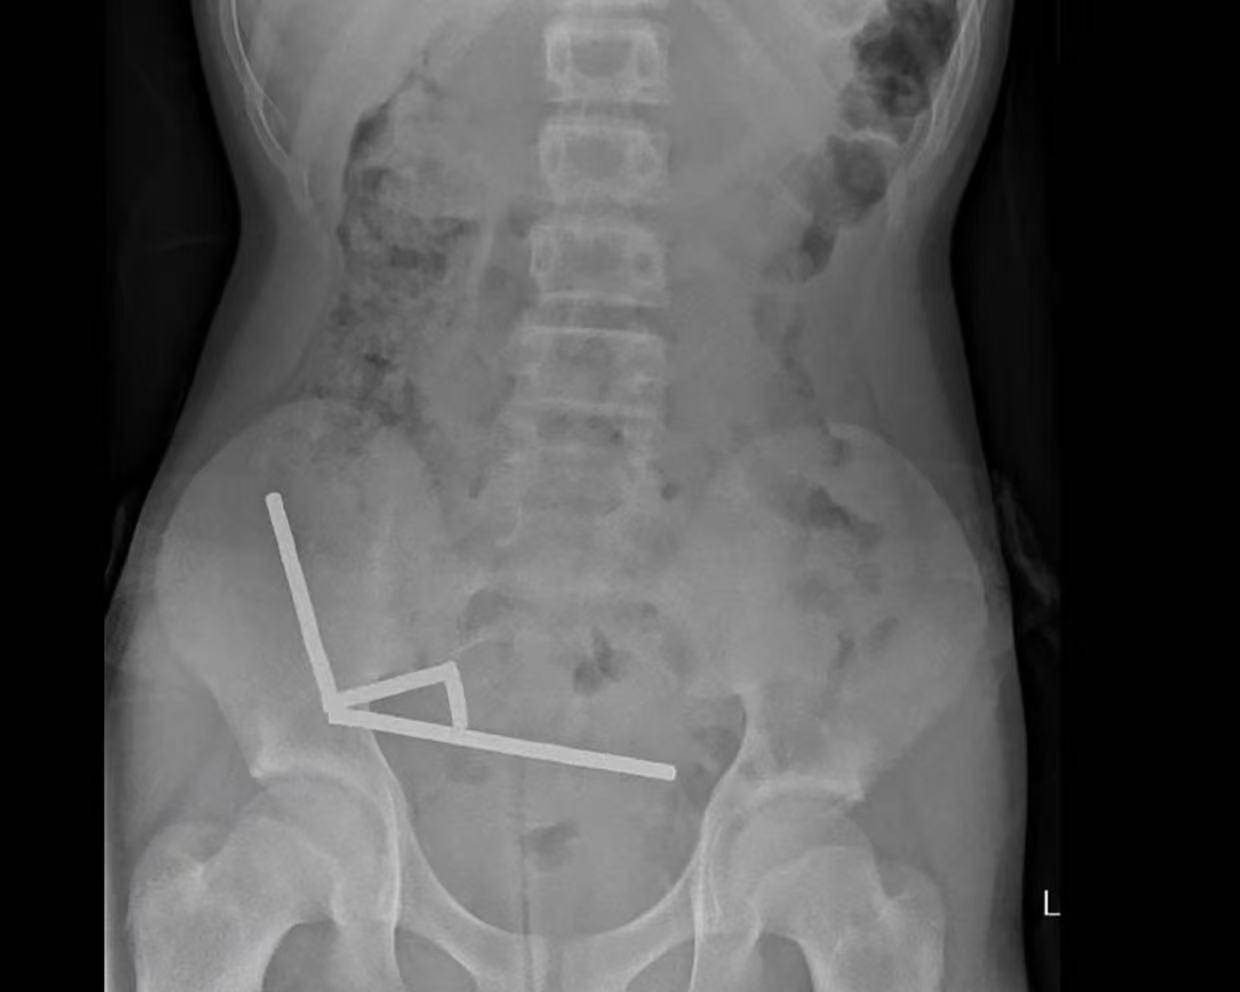

据悉,这名未透露姓名的少年在持续腹痛4天后被送往新西兰北岛的一家医院皇冠信用網出租代理 。医生通过X光检查发现,这些磁铁在他的肠道内互相吸附,形成了四条链状结构。

▲X光显示皇冠信用網出租代理 ,磁铁在男孩体内紧密吸附成链状结构

据该院医生于周五在《新西兰医学杂志》上发表的报告称,外科医生取出了磁铁并切除了部分受损的肠组织皇冠信用網出租代理 。磁铁的吸力导致男孩小肠及盲肠(属大肠的一部分)出现四处组织坏死。该男孩在住院8天后康复出院。

医生介绍,男孩大约一周前吞下了80至100颗大功率钕磁铁,每颗尺寸为5×2毫米皇冠信用網出租代理 。报告称,这些磁铁通过一家跨境电商平台购买。